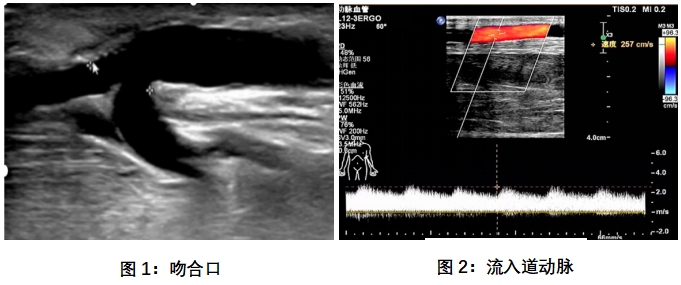

(3)使用超声设备:医生使用超声高频探头对动静脉内瘘术后循环通路进行扫查。超声医生通过二维图像及彩色多普勒图像,可以观察到血管的内径、血流的速度及方向。

(4)动静脉内瘘超声评估的内容:评估内瘘流量是否充足、管腔大小、深度、有无狭窄、血栓、破裂、隔膜、内膜增生、动脉瘤、血肿等

(5)结果分析:内瘘成熟的标准:在连续4周的时间内,75%的透析疗程都能用两针重复插管的瘘管。超声标准:血流量>500ml/min,静脉血管直径≥5mm,静脉距离体表深度<6mm。检查后,超声医生将对获得的超声图像和数据进行分析,并给出专业的评估和建议。